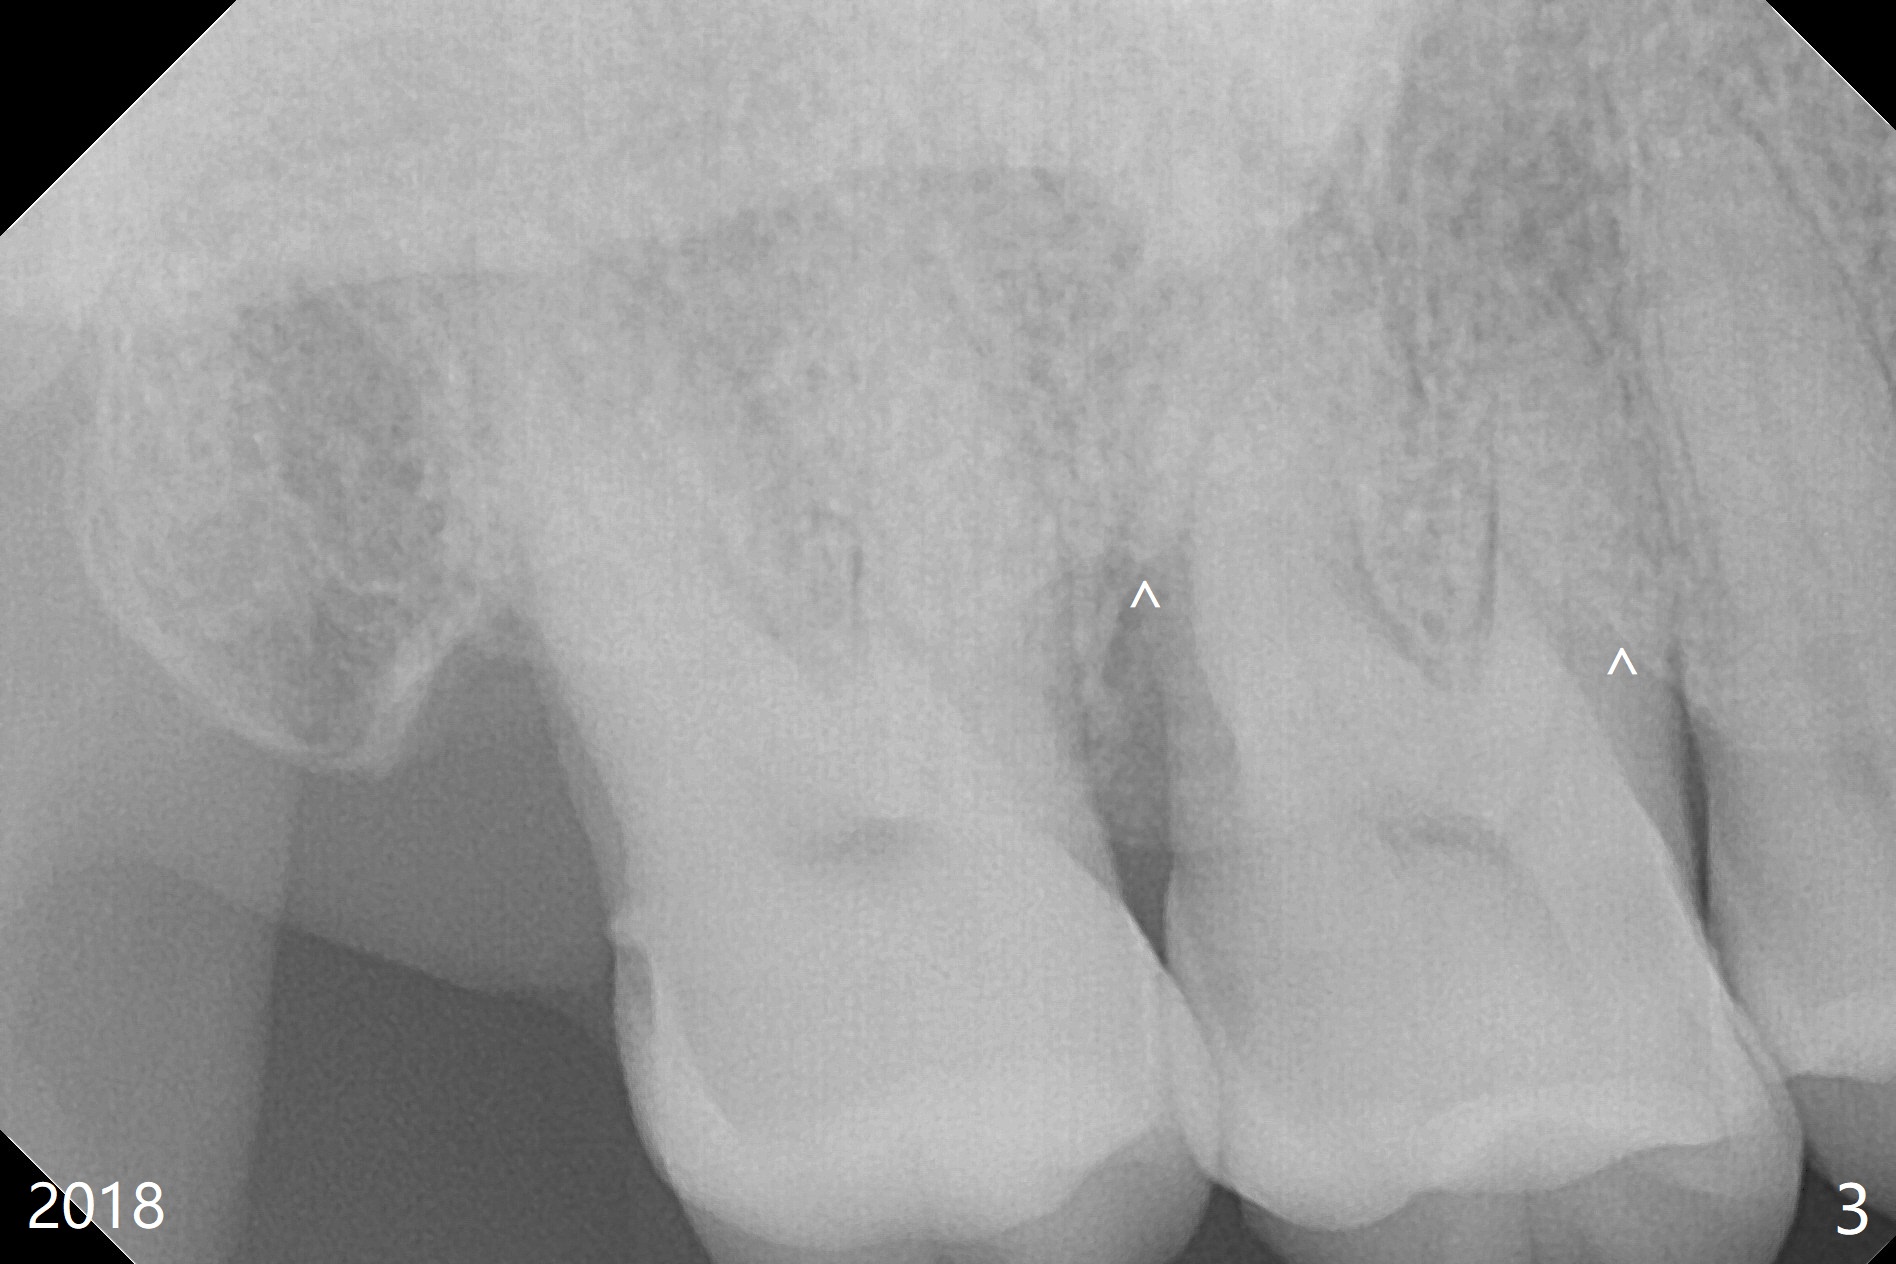

A 65-year-old woman has had signs & symptoms of crack tooth at #3 for the last 4 years (Fig.1-3). Finally the tooth is tender for mastication. Since the socket has infection and the bone is long (Fig.4 red line), an implant will be placed shy of the sinus floor (yellow dashed line). The bone loss (Fig.2,3 ^) may be associated with bruxism, which is detrimental to implant osteointegration. The immediate provisional should have enough occlusal clearance.